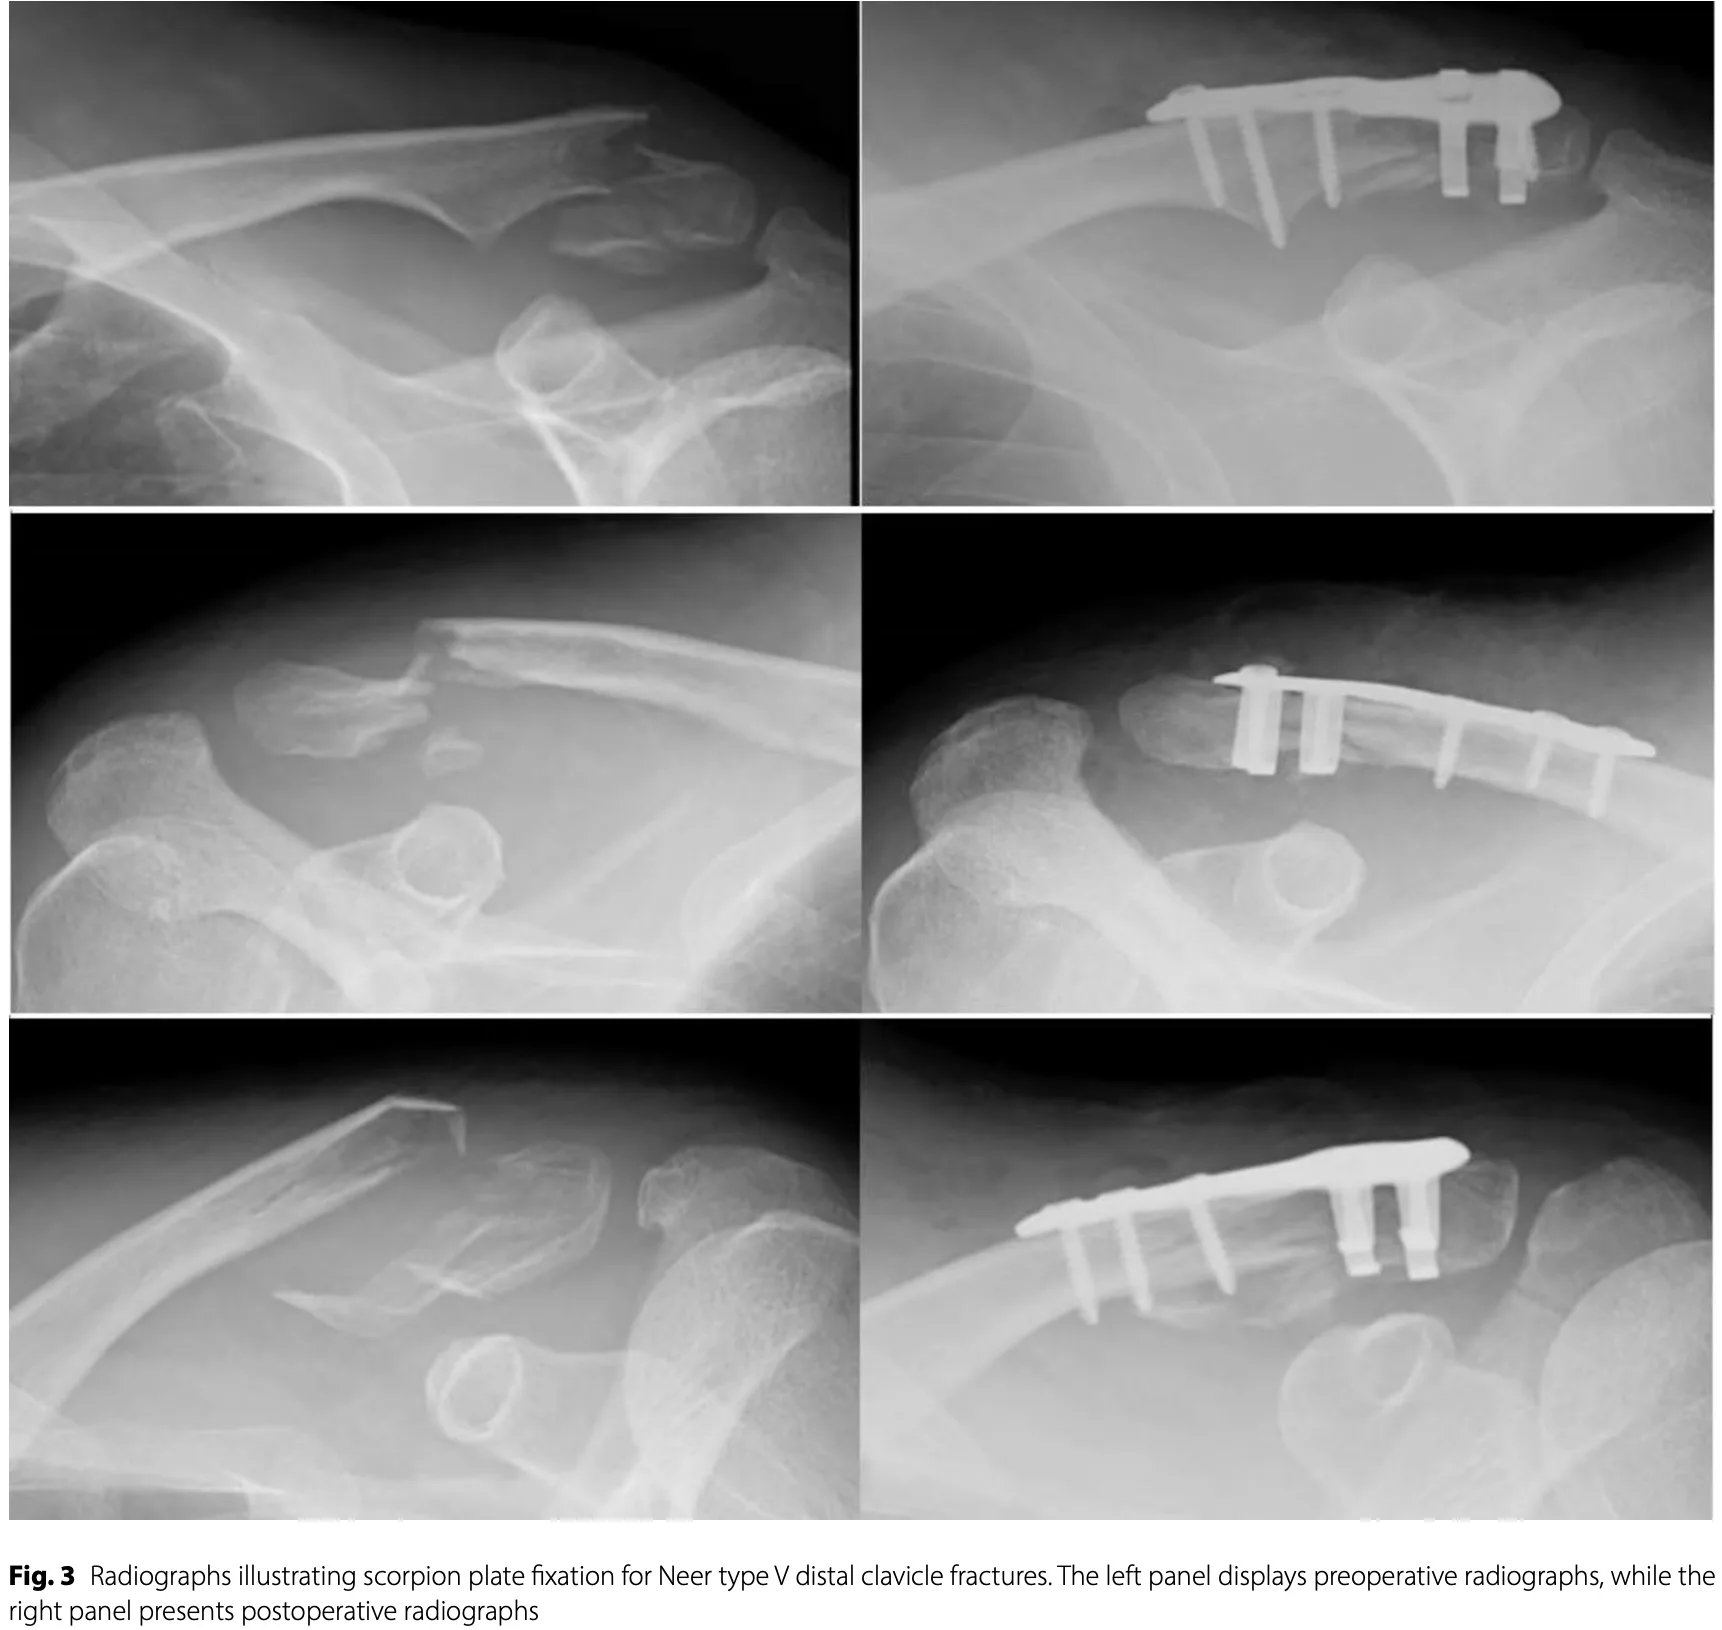

中高年の鎖骨遠位部骨折に対する手術でした.

後輩医師の執刀で, 大学から診療応援に来られた医師が指導に入り, 自分は現場監督に.

スコーピオンネオ(SCORPION® NEO)というプレートを使って, ズレた鎖骨を元の位置に戻して, ネジで固定.

さらに人工靱帯で補強しました.

初めての手術だったので, 少し時間がかかりましたが, 予定通りにしっかり固定できました.